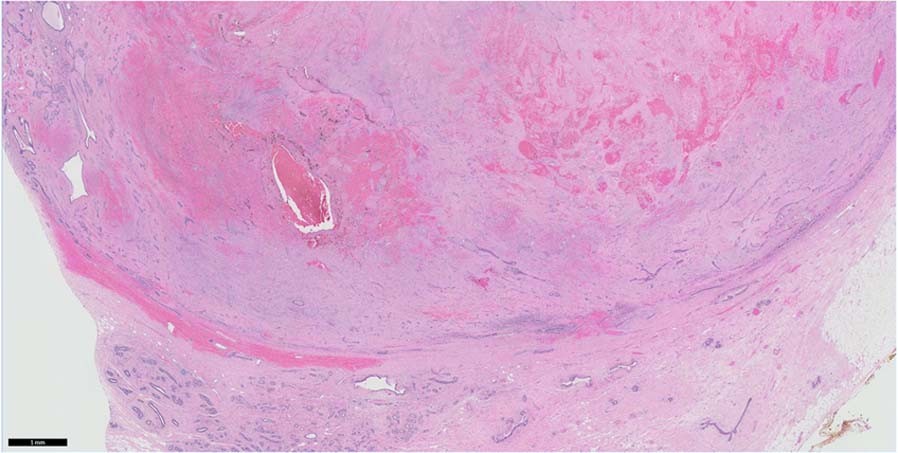

Fig. 2: Infarction in a fibroadenoma shows haemorrhage and loss of cellular detail.

The circumscribed boundary of the fibroadenoma with adjacent breast tissue is seen in the lower half of the field.